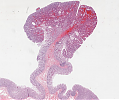

A60 Plattenepithelpapillom

Papillär aufgefaltetes Plattenepithel mit Akanthose.